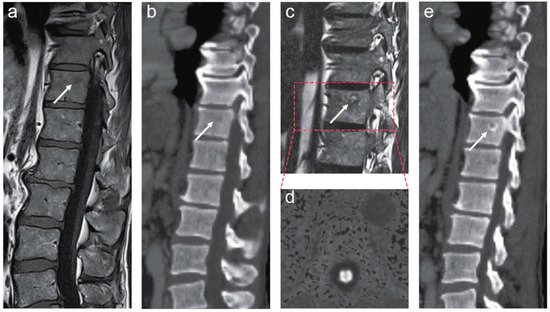

We report the case of a 68-year-old man who was diagnosed with de novo mPCa T3bN+M1a+b stage in November of 2019. The patient had no family history of PCa. The pathology report showed a Gleason score of 9, grade group 5 in all 10 biopsies at diagnosis. Morphologically, intraductal carcinoma was the dominant cell pattern, while cribriform and perineural growth were observed in the pathological examination [10]. The pretreatment prostate-specific antigen (PSA) level was 13 ng/mL. Multiparametric magnetic resonance imaging (mpMRI) and prostate-specific membrane antigen (PSMA)-positron emission tomography (PET)/computed tomography (CT) confirmed the tumor spread to the pelvic lymph nodes and a possible solitary metastasis to one of the thoracic vertebrae (Figure 1). The immunohistochemical analysis of primary tumor biopsies revealed the expression of all MMR proteins and was negative for PD-L1 staining but showed focal CD3 positivity.

Figure 1. Magnetic resonance imaging (MRI) and prostate-specific membrane antigen (PSMA)-positron emission tomography (PET)/computed tomography (CT) findings at the baseline. Axial T2-weighted MRI sequences demonstrated a large, diffuse infiltrating tumor in the peripheral zone with seminal vesicle invasion ((a,b), white arrows). The tumor was hyperintense on diffusion-weighted MRI (DW-MRI) (b = 1500 s/mm2) ((c,d), white arrows) with a corresponding low apparent diffusion coefficient (ADC) (ADC = 0.6 × 10−3 mm2/s) ((e,f), white arrows). Corresponding tracer uptake on fused PSMA-PET/CT images ((g,h), white arrow). A large lymph node metastasis in the mesorectal fat is shown on the axial T2-weighted MRI ((i), white arrow) and fused PSMA-PET/CT images ((j), white arrow). A coronal-fused PSMA-PET/CT image demonstrates multiple metastases to the pelvic lymph nodes ((k), white arrows).